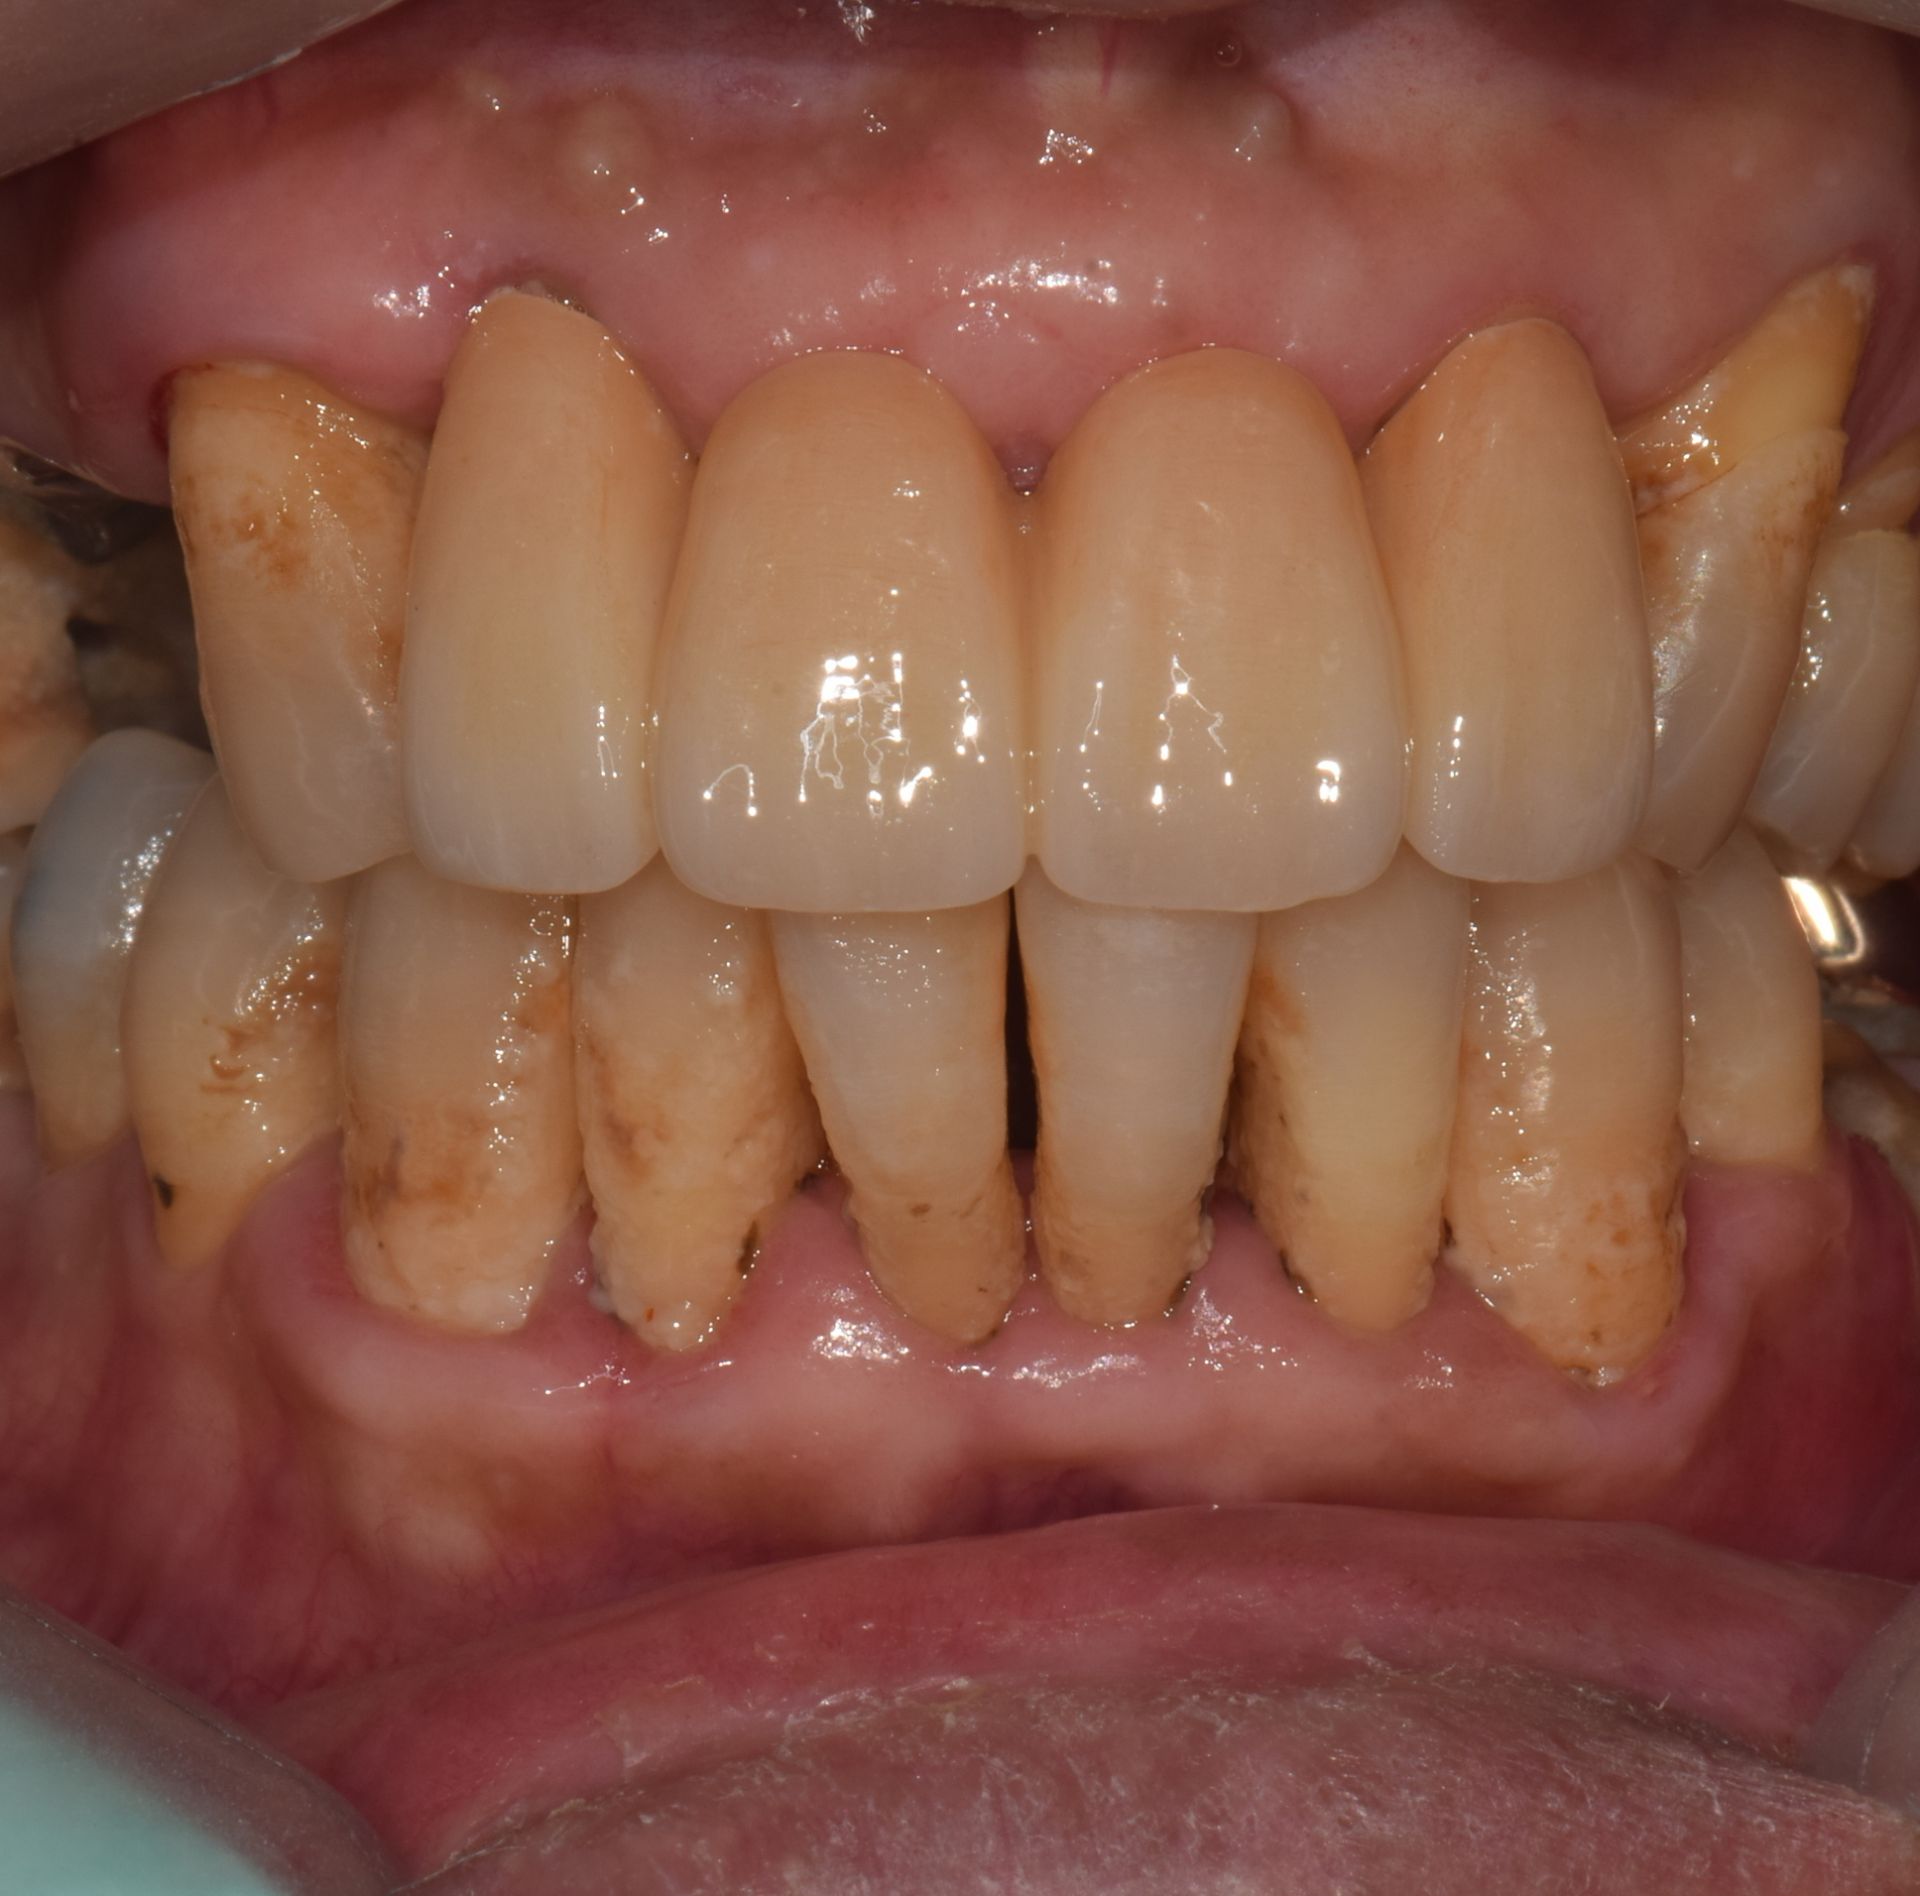

치아우식, 신경치료 및 치은성형술, 심미보철치료

치료 기간 2023. 11. 02 ~ 2023. 12. 20

확장 개원 후 마무리하신 환자분입니다. 앞니 기존 보철물을 하고 계셨지만 치아가 삭아서 보철물이 탈락해서 내원하셨습니다. 환자분께서는 뽑고 임플란트를 생각하고 오셨지만...

“치아는 살릴 수 있다면, 살리는 게 좋다.”

간단한 잇몸 수술, 신경치료 후에 기둥을 세워 치아머리만 만들어진다면 충분히 살릴 수 있다고 판단하고 살리는 쪽으로 설명드렸습니다. 환자분들의 치아 하나하나를 소중히 생각하는 참조은치과입니다.

* 상기 사진은 본원 권대근 대표원장이 치료한 환자분의 동의를 받은 이미지 사진으로 실제와 차이가 있을 수 있습니다.